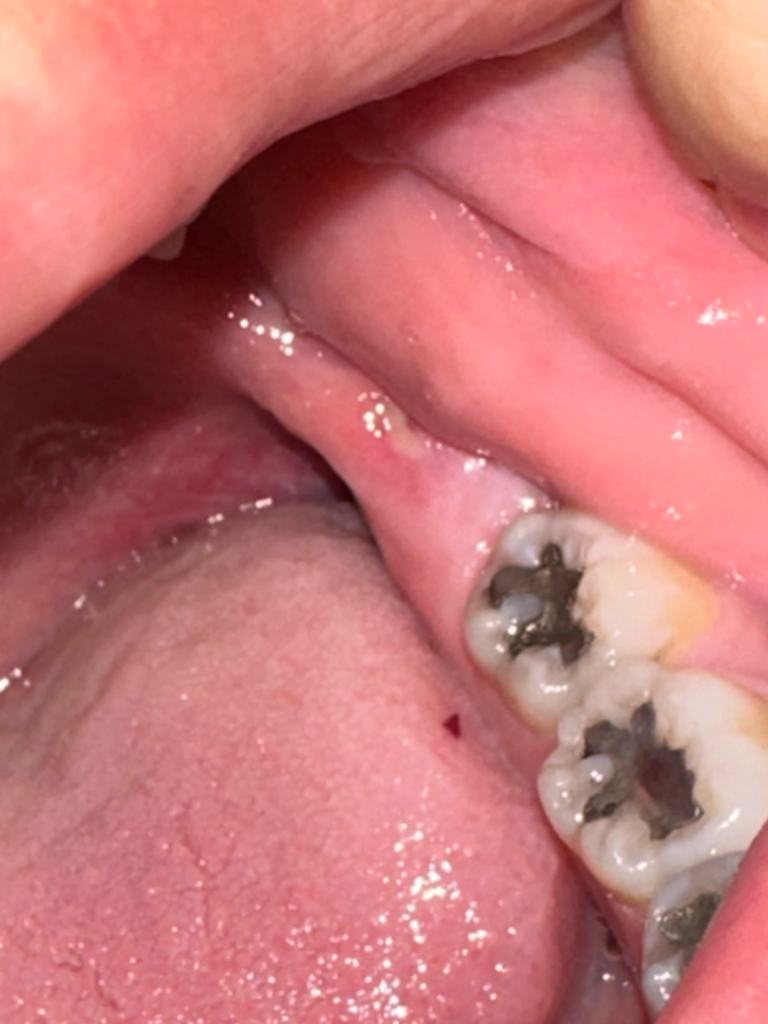

단순 구내염보다는 전반적인 잇몸 염증일 가능성이 높아보입니다. 치과를 가보시는 게 좋겠습니다.

해당 잇몸에 반대 부위에 부위에 사랑니가 올라와 있거나 사랑니에 뾰족한 부분이 아래를 누르게 된다면 해당 부위에 구내염이 생길 수 있습니다.

이런 경우에는 눌리고 있는 부위의 사랑니를 발치해주거나 뾰족한 부위를 다듬어주면 괜찮아지는 경우도 있습니다. 자세한 확인을 위해서 치과에서 진료를 받아보는 것을 권유드립니다.

몸이 피곤하거나 그럴경우에는 몸의 면역력이 떨어지면서 구내염이 발생할수 잇습니다. 사진상에 보이는건 구내염이신거 같습니다. 시간이 지나면 괜찮아 지실꺼에요.

현재 사진상 구내염 의 가능성 및 잇몸 염증의 가능성이 있습니다. 소독용 가글액인 탄툼가글액을 사용하여 보길 권하며 해당 부위 통증 및 붓기가 더 심해지는 경우 치과 진료를 받아보길 바랍니다.